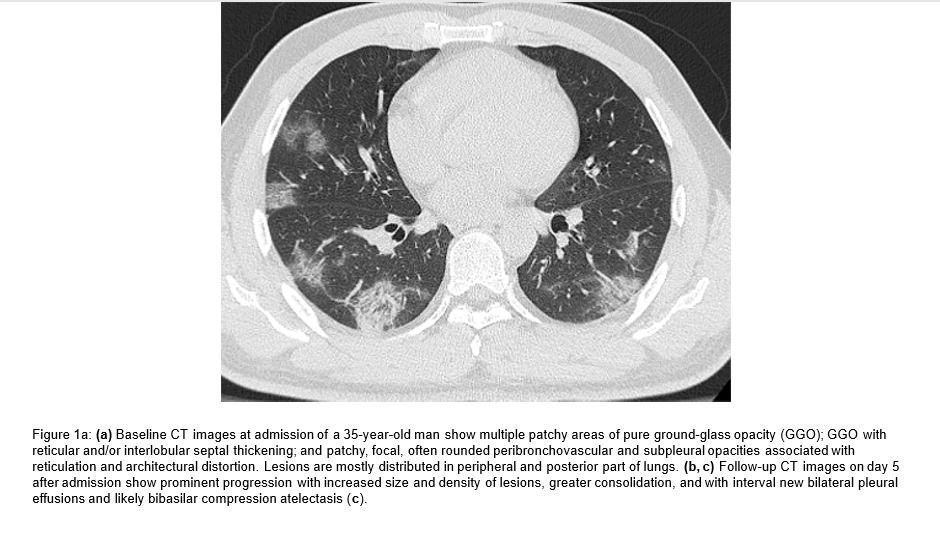

Imaging Findings

CT and Ultrasound findings of infected people are similar to other inflammatory, viral and bacterial respiratory syndromes. These are non-specific or pathognomic for Covid-19.

According to one study CT images showed pure ground-glass opacity (GGO) in 39 of 51 (77%) patients and GGO with reticular and/or interlobular septal thickening in 38 of 51 (75%) patients. GGO with consolidation was present in 30 of 51 (59%) patients, and pure consolidation was present in 28 of 51 (55%) patients. Forty-four of 51 (86%) patients had bilateral lung involvement.